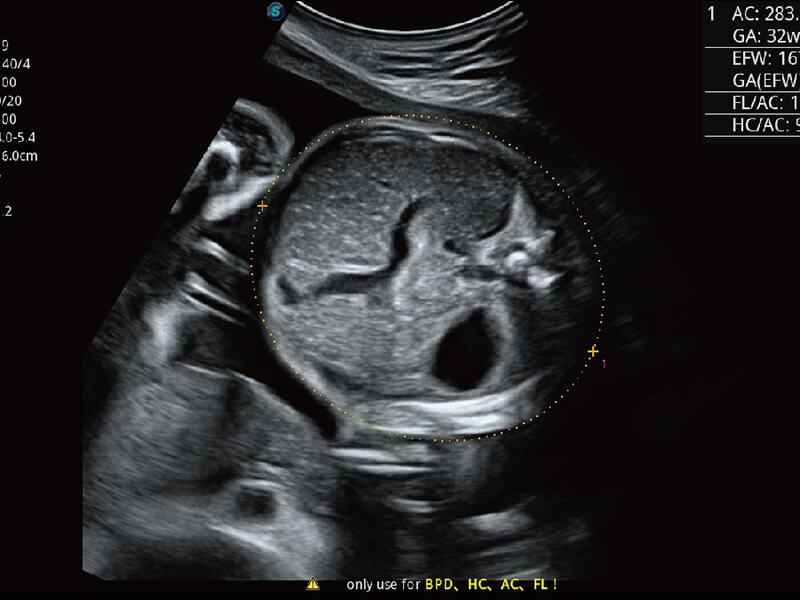

S60探头工艺,从前端信号处理每一个环节采集无损声学数据,真实还原组织原貌,再现解剖细节。

高分辨率容积成像 栩栩如生

超宽频带技术,为容积成像带来优质的二维图像基础,为您呈现丰富的结构细节,栩栩如生地展示宝宝的宫内形态以及各种组织的立体结构。